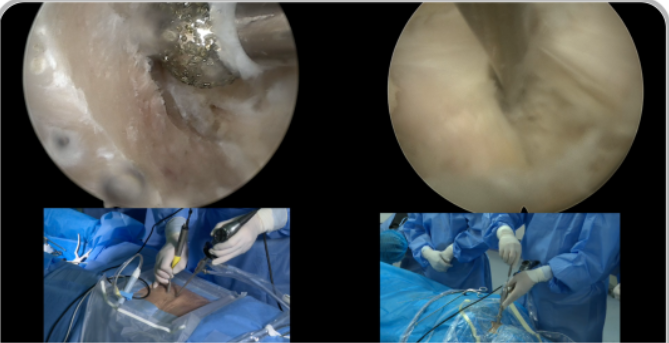

山東奧蘇本UBE/BESS雙通道脊柱內(nèi)鏡微創(chuàng)手術(shù)系統(tǒng)生產(chǎn)廠家產(chǎn)品說明:

雙通道脊柱內(nèi)鏡技術(shù)(BESS/UBE)手術(shù)適應(yīng)癥

1. 普通椎間盤突出、極外側(cè)間盤突出;

2. 中央椎管狹窄、側(cè)隱窩狹窄、椎間孔狹窄;

3. 頸椎、腰椎、胸椎的退行性形變;

4. 退行性滑脫(BE-TLIF) ;

5. 腰椎翻修病例;

6. 神經(jīng)根型頸椎病、脊髓型頸椎病

UBE脊柱內(nèi)鏡手術(shù)用全套器械包括: